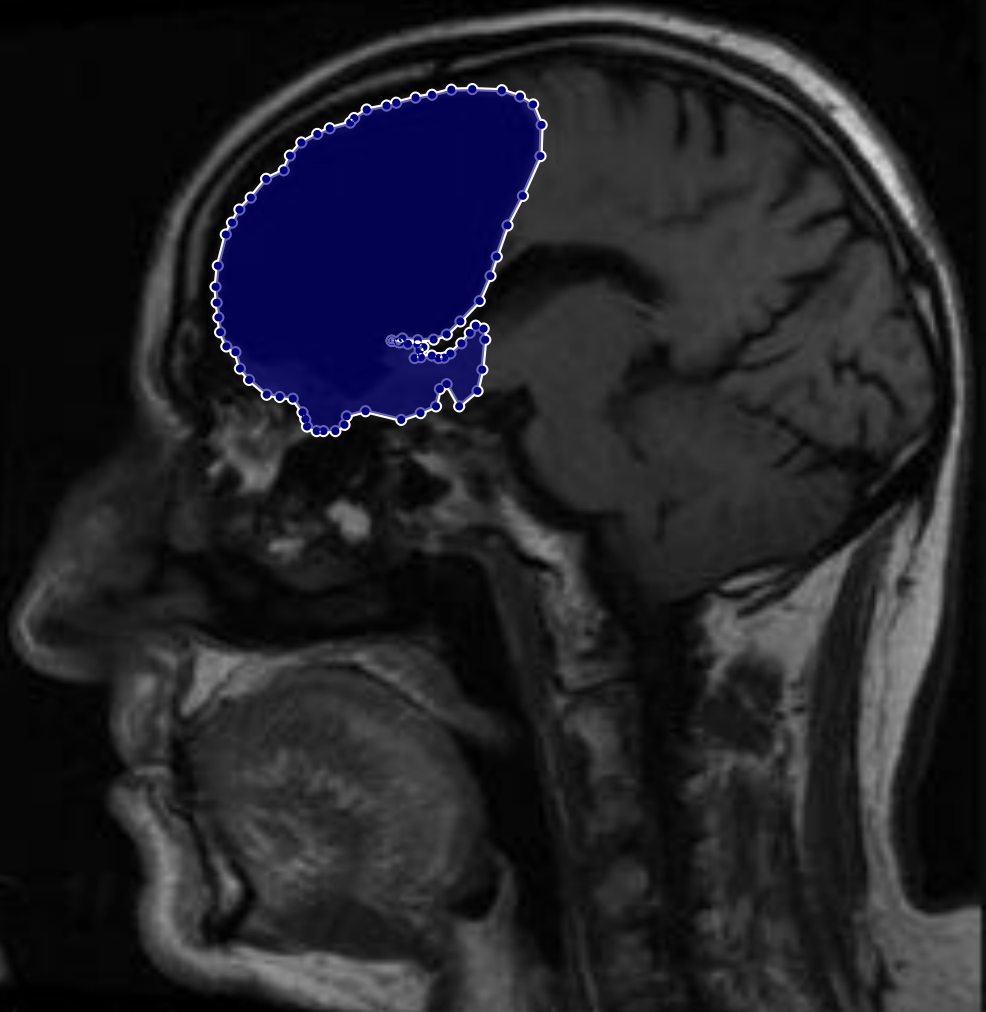

Figure 2: Samples of Meningioma segmentation across different imaging planes

Meningioma: Meningiomas arise from the meninges and are generally well‑circumscribed and homogeneous, making them easier to segment. However, their location adjacent to critical structures such as dural sinuses and cranial nerves can complicate diagnostic tasks. An example of a meningioma and its segmentation mask is presented in Figure 2, illustrating the clarity of its boundaries.